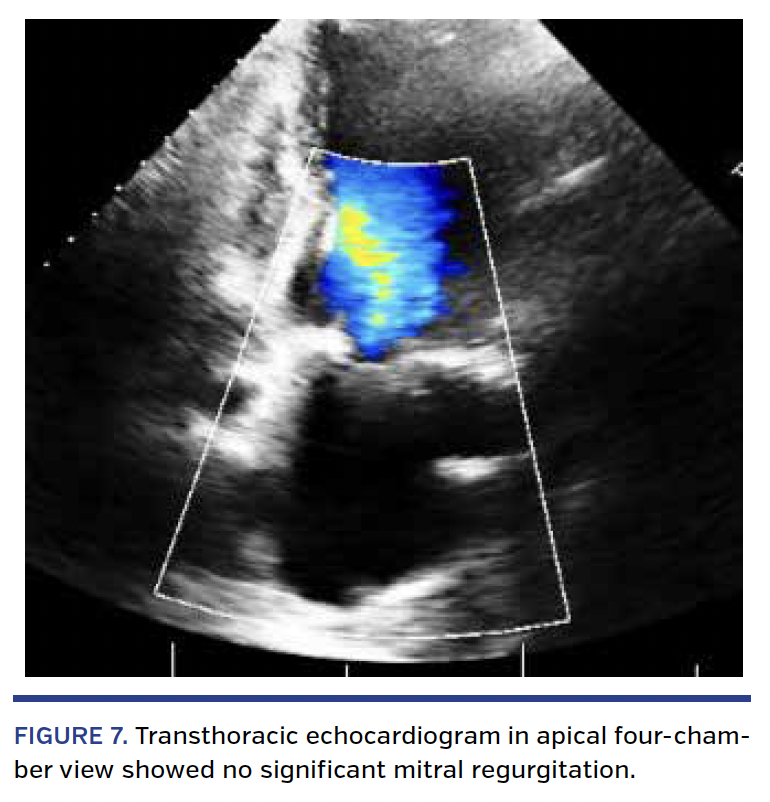

Second TAVR. As with the first TAVR procedure, the second TAVR procedure was completed under general anesthesia via transfemoral route. TEE was also used to guide the procedure. No dilation of the first TAVR valve was planned. The Sapien XT valve was prepared as usual but with an additional 2 cc of volume in the balloon. The CoreValve was crossed without difficulty and a properly curved extra-stiff Amplatzer wire was advanced into the left ventricle. The Sapien XT valve was prepared and advanced across the CoreValve without difficulty. The positioning was set at a level of 2-4 mm from the lower edge of the CoreValve. With proper positioning, rapid pacing was initiated. At a systolic blood pressure <50 mm Hg and pulse pressure <10 mm Hg, the Sapien XT valve was deployed slowly and remained in the targeted position (Figure 5). TEE immediately post TAVR showed resolution of the central aortic regurgitation. In addition, there was near complete resolution of the PVL (Figure 6). A follow-up aortogram demonstrated that the coronary arteries were widely patent, as well as a significant reduction in his mitral valve regurgitation (Figure 7).